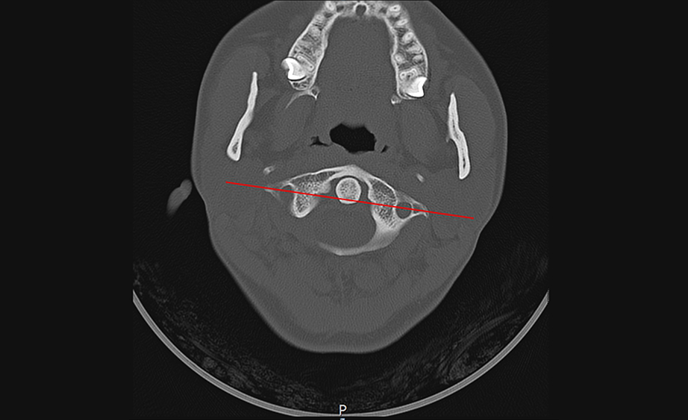

▲ 치료 전 (2016년 1월 21일)

▲ CTA 5개월 착용 (2016년 6월 29일)

▲ CTA 9개월 착용 (2016년 10월 29일)